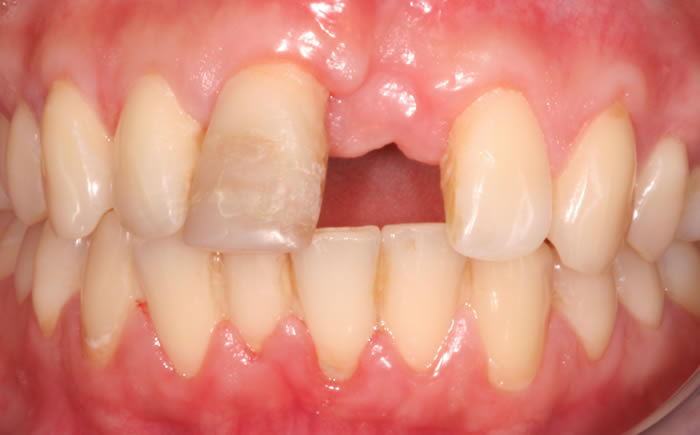

Dental implants used to replace two upper front teeth

Missing upper front tooth replaced by dental implant and crown